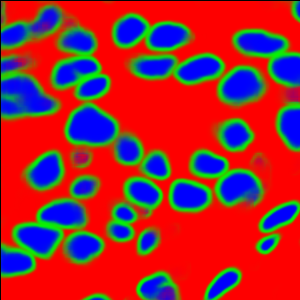

The task of nuclei segmentation can be roughly divided into two stages: the first stage is extracting the foreground(nuclei), the second stage is segmenting the connected foreground area into separated nuclei and finding out the boundary of each nucleus. Our method intends to merge these two steps by extracting the nuclei and their edges at the same time. That is the reason why it is named ”nuclei-boundary(NB) model”. As shown in Fig.3, the output of the NB model has three channels, each has the same height and width with the input image. Its values represent the probabilities of each pixel being , or class, respectively. The manual annotation for our segmentation problem is the boundary of each nucleus. A pixel belonging to the class means that it is on or inside an annotated boundary and within 2 pixel from the boundary. Pixels of the class are those that are inside annotated boundary but are not pixels. Correspondingly, the output can be regarded as an RGB image and the estimated maps of the , and are represented by red, green and blue, respectively, as shown in Fig.3. To generate the ternary mask for training, we apply a morphology operator to each nucleus to obtain the pixels, and then subtract pixels from the nucleus to get pixels.

Figure 6 shows how our method segments the nuclei step by step. The color variety is well controlled by the color normalization procedure. The prediction result shows clear nuclear areas and nucleus boundaries. In the final segmentation result and ground truth image, each nucleus is represented by a different color.